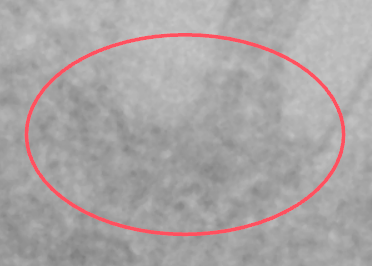

Results of the periapical radiolucency (PRL) analysis - Red circles/ovals appear on the image where possible signs of inflammatory bone lesions around the root apices of teeth were detected.